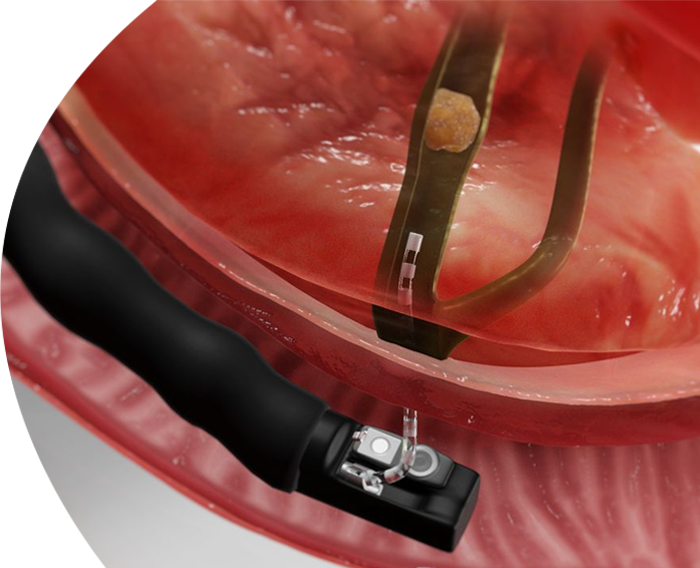

منظار القولون

منظار القولون هو إجراء طبي يتم فيه استخدام أنبوب مرن مزود بكاميرا لرؤية الجزء الداخلي من الأمعاء الغليظة (القولون والمستقيم) بهدف التشخيص أو العلاج، ويكشف عن مشاكل مثل الزوائد اللحمية، الأورام، التهابات القولون، أو نزيف المستقيم، ويمكن للطبيب خلاله أخذ عينات من الأنسجة (خزعات) أو استئصال بعض الزوائد الحميدة.